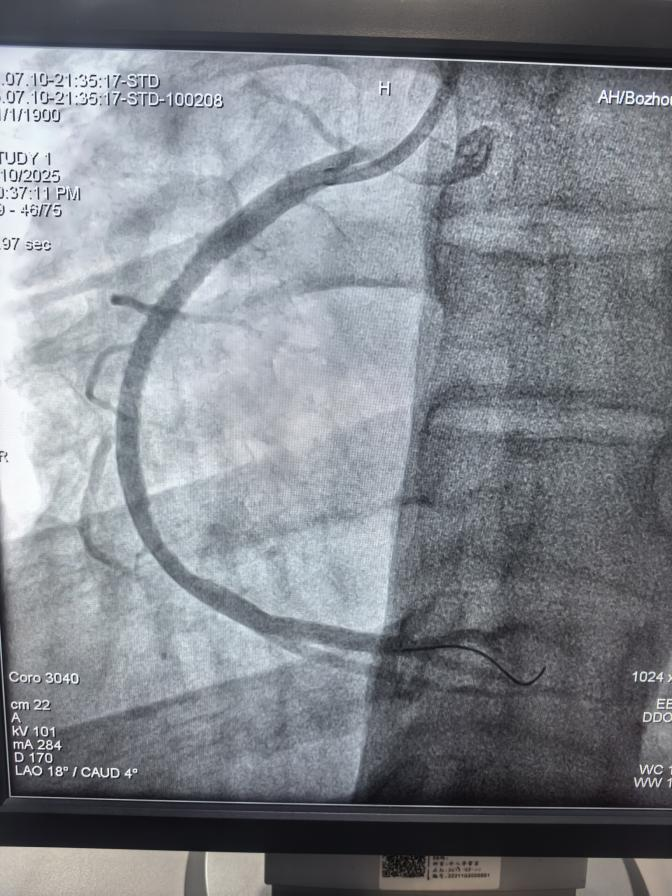

支架植入后,血管流通